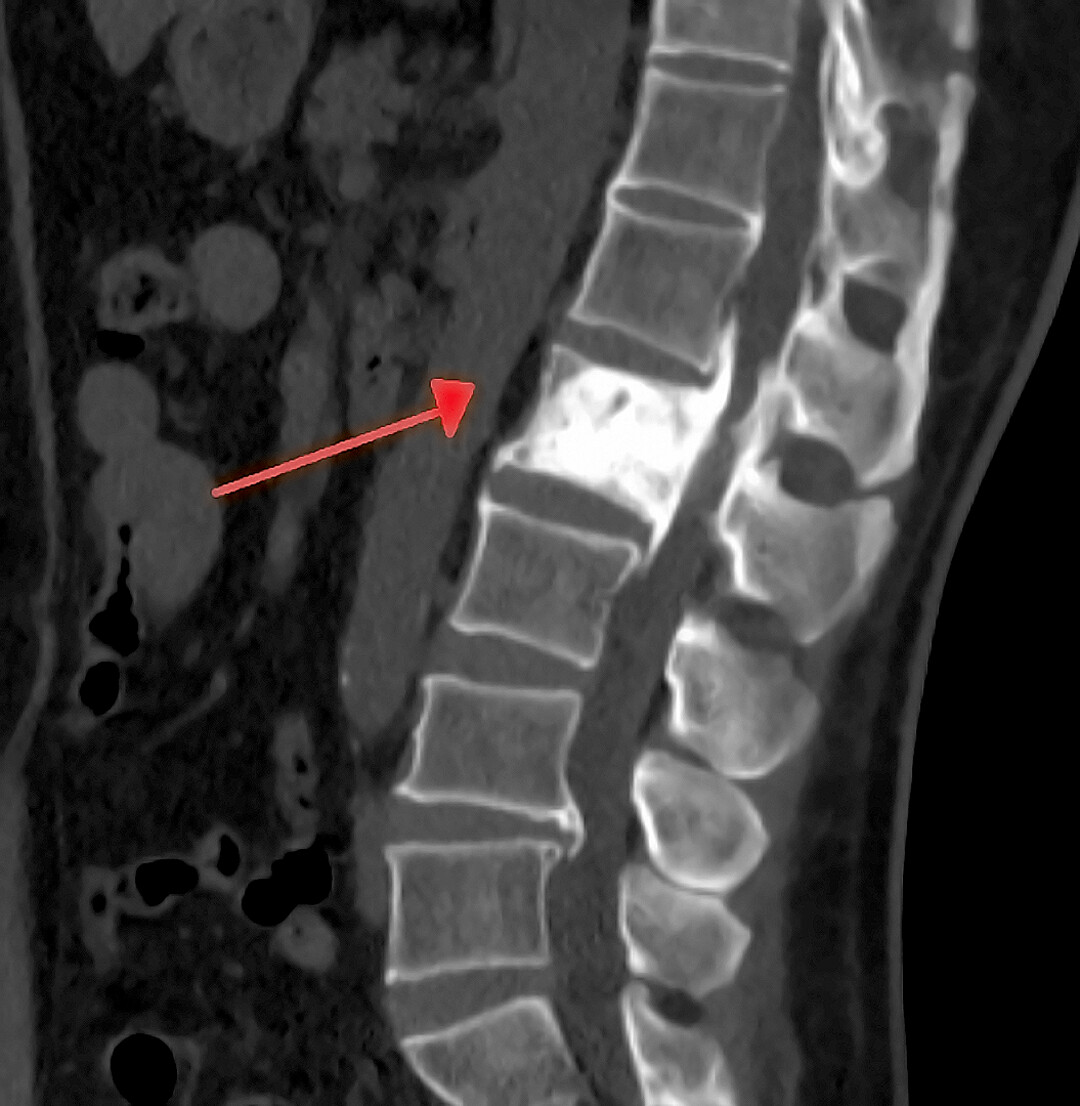

From orthopaedicprinciples.com

Paget’s Disease Of The Spine — Paget's Disease Symptoms Adults Many people with paget’s disease do not have symptoms. Paget’s disease of the bone (osteitis deformans) is a chronic bone disorder characterized by excessive breakdown and regrowth in the. Symptoms of a nerve problem,. It causes bones to become enlarged and deformed. Paget's disease of bone is a chronic disease of the skeleton. The symptoms appear slowly over time, and. Paget's Disease Symptoms Adults.